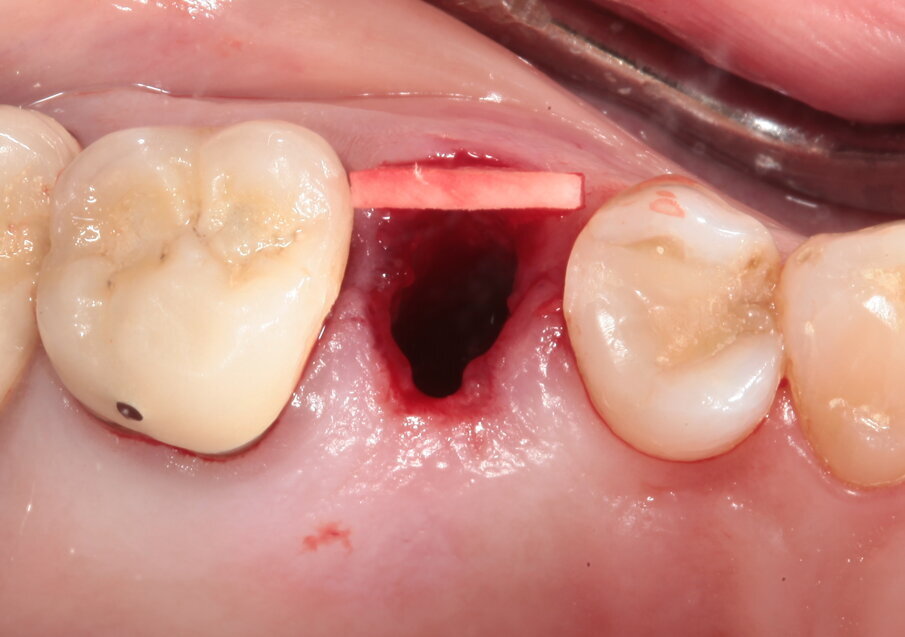

Il piano di trattamento prevede quindi l’estrazione del 25 giudicato non mantenibile, la preservazione dell’alveolo post estrattivo, l’inserimento differito di un impianto e il suo carico una volta terminato il processo di osteointegrazione. Per quanto riguarda l’elemento 24, si programma la terapia endodontica e la successiva ricostruzione diretta. Viene effettuata un’estrazione atraumatica del 25, la rimozione del tessuto infiammatorio periapicale e il posizionamento di un sostituto osseo addizionato con acido ialuronico reticolato ad alto peso molecolare (HyaDENT BG) al fine di ottenere una più rapida stabilizzazione del coagulo ed una buona stabilità dell’innesto, determinanti per il mantenimento del volume ottimale. Questo viene poi coperto con una membrana di collagene suino imbustata al di sotto dei tessuti vestibolari e palatali (Figg. 6-10).